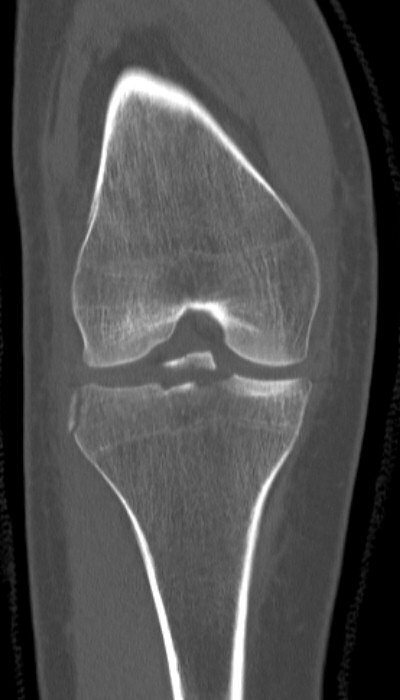

Första bilden eminentiafraktur typ III (och segondfraktur), andra bilden efter operation med sutur.